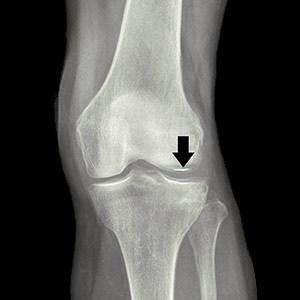

Insufficiency Fracture of the Knee

Insufficiency fracture of the knee, also referred to as subchondral insufficiency fracture of the knee (SIFK), is a type of stress fracture that occurs when excessive and repetitive stress is applied to the femoral condyles or tibial plateau of the knee.